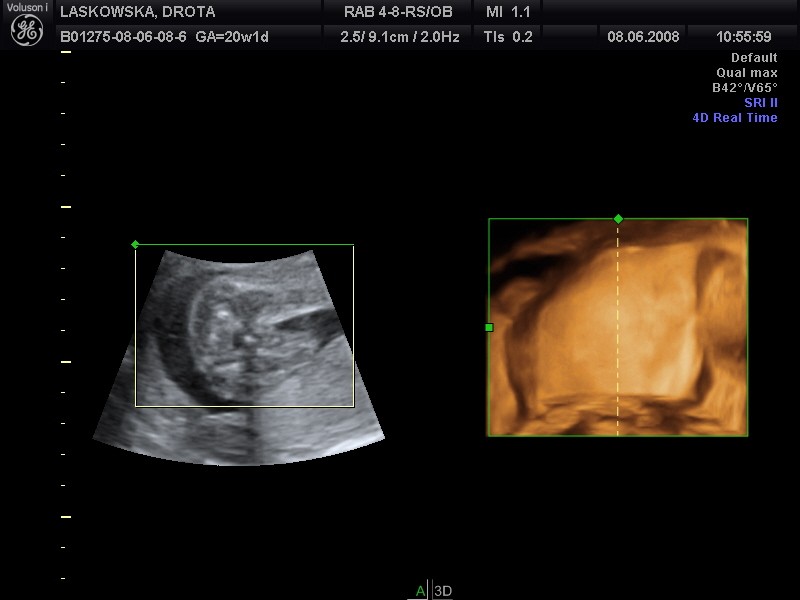

A tu pozwoliłam soebie wkleić Twoje fotki tzn Oliwii:-p

Piękne foty:tak:

Załączniki

• laskowska12nj8.jpg

laskowska12nj8.jpg

50,9 KB · Wyświetleń: 46